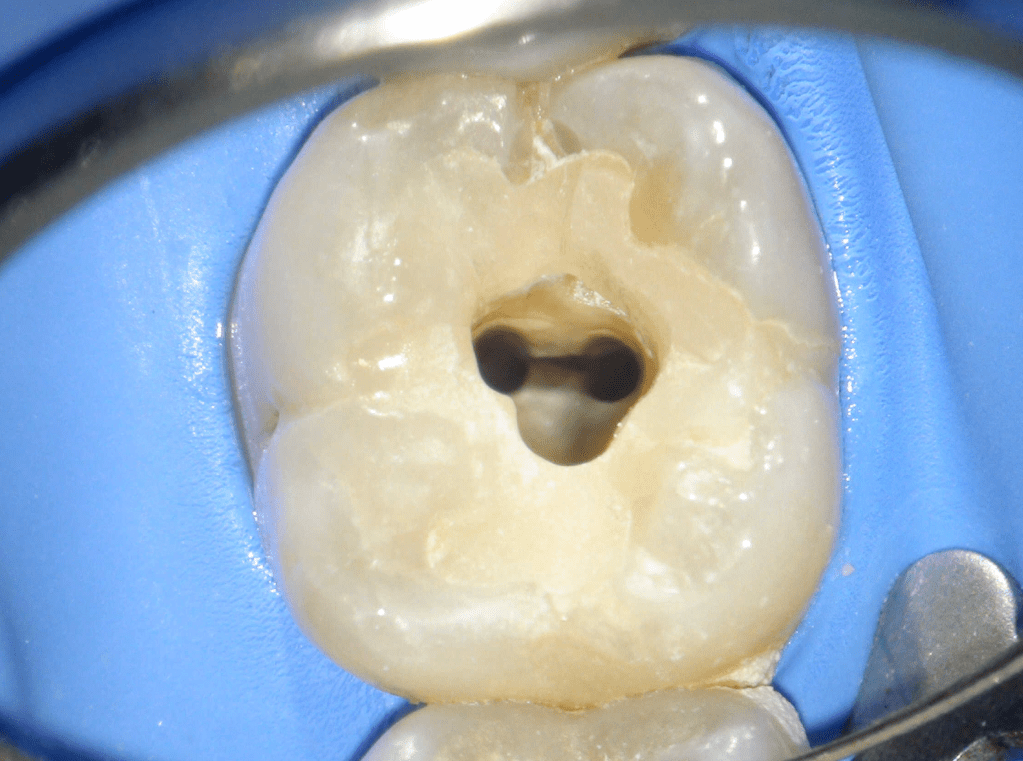

Reco preendo + 4 conductos molar superior